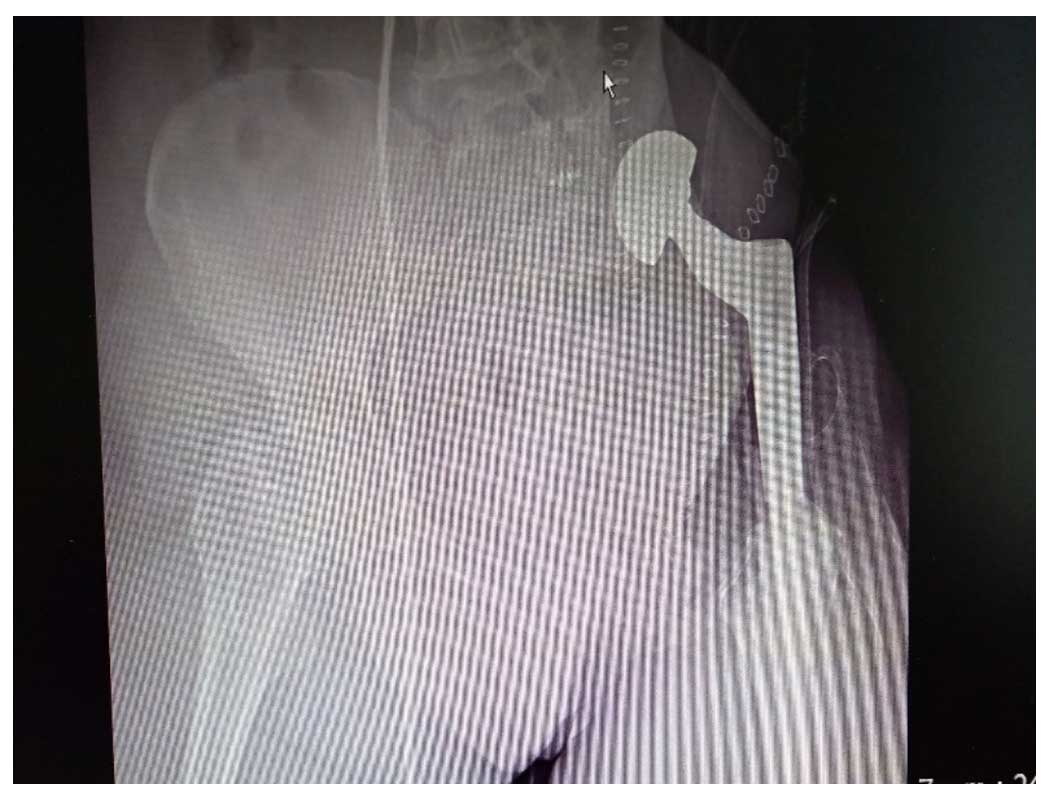

Ameliyat Sonrası: Röntgende internal hemipelvektomi sonrası protez ile kalça transpozisyonu görülmekte.